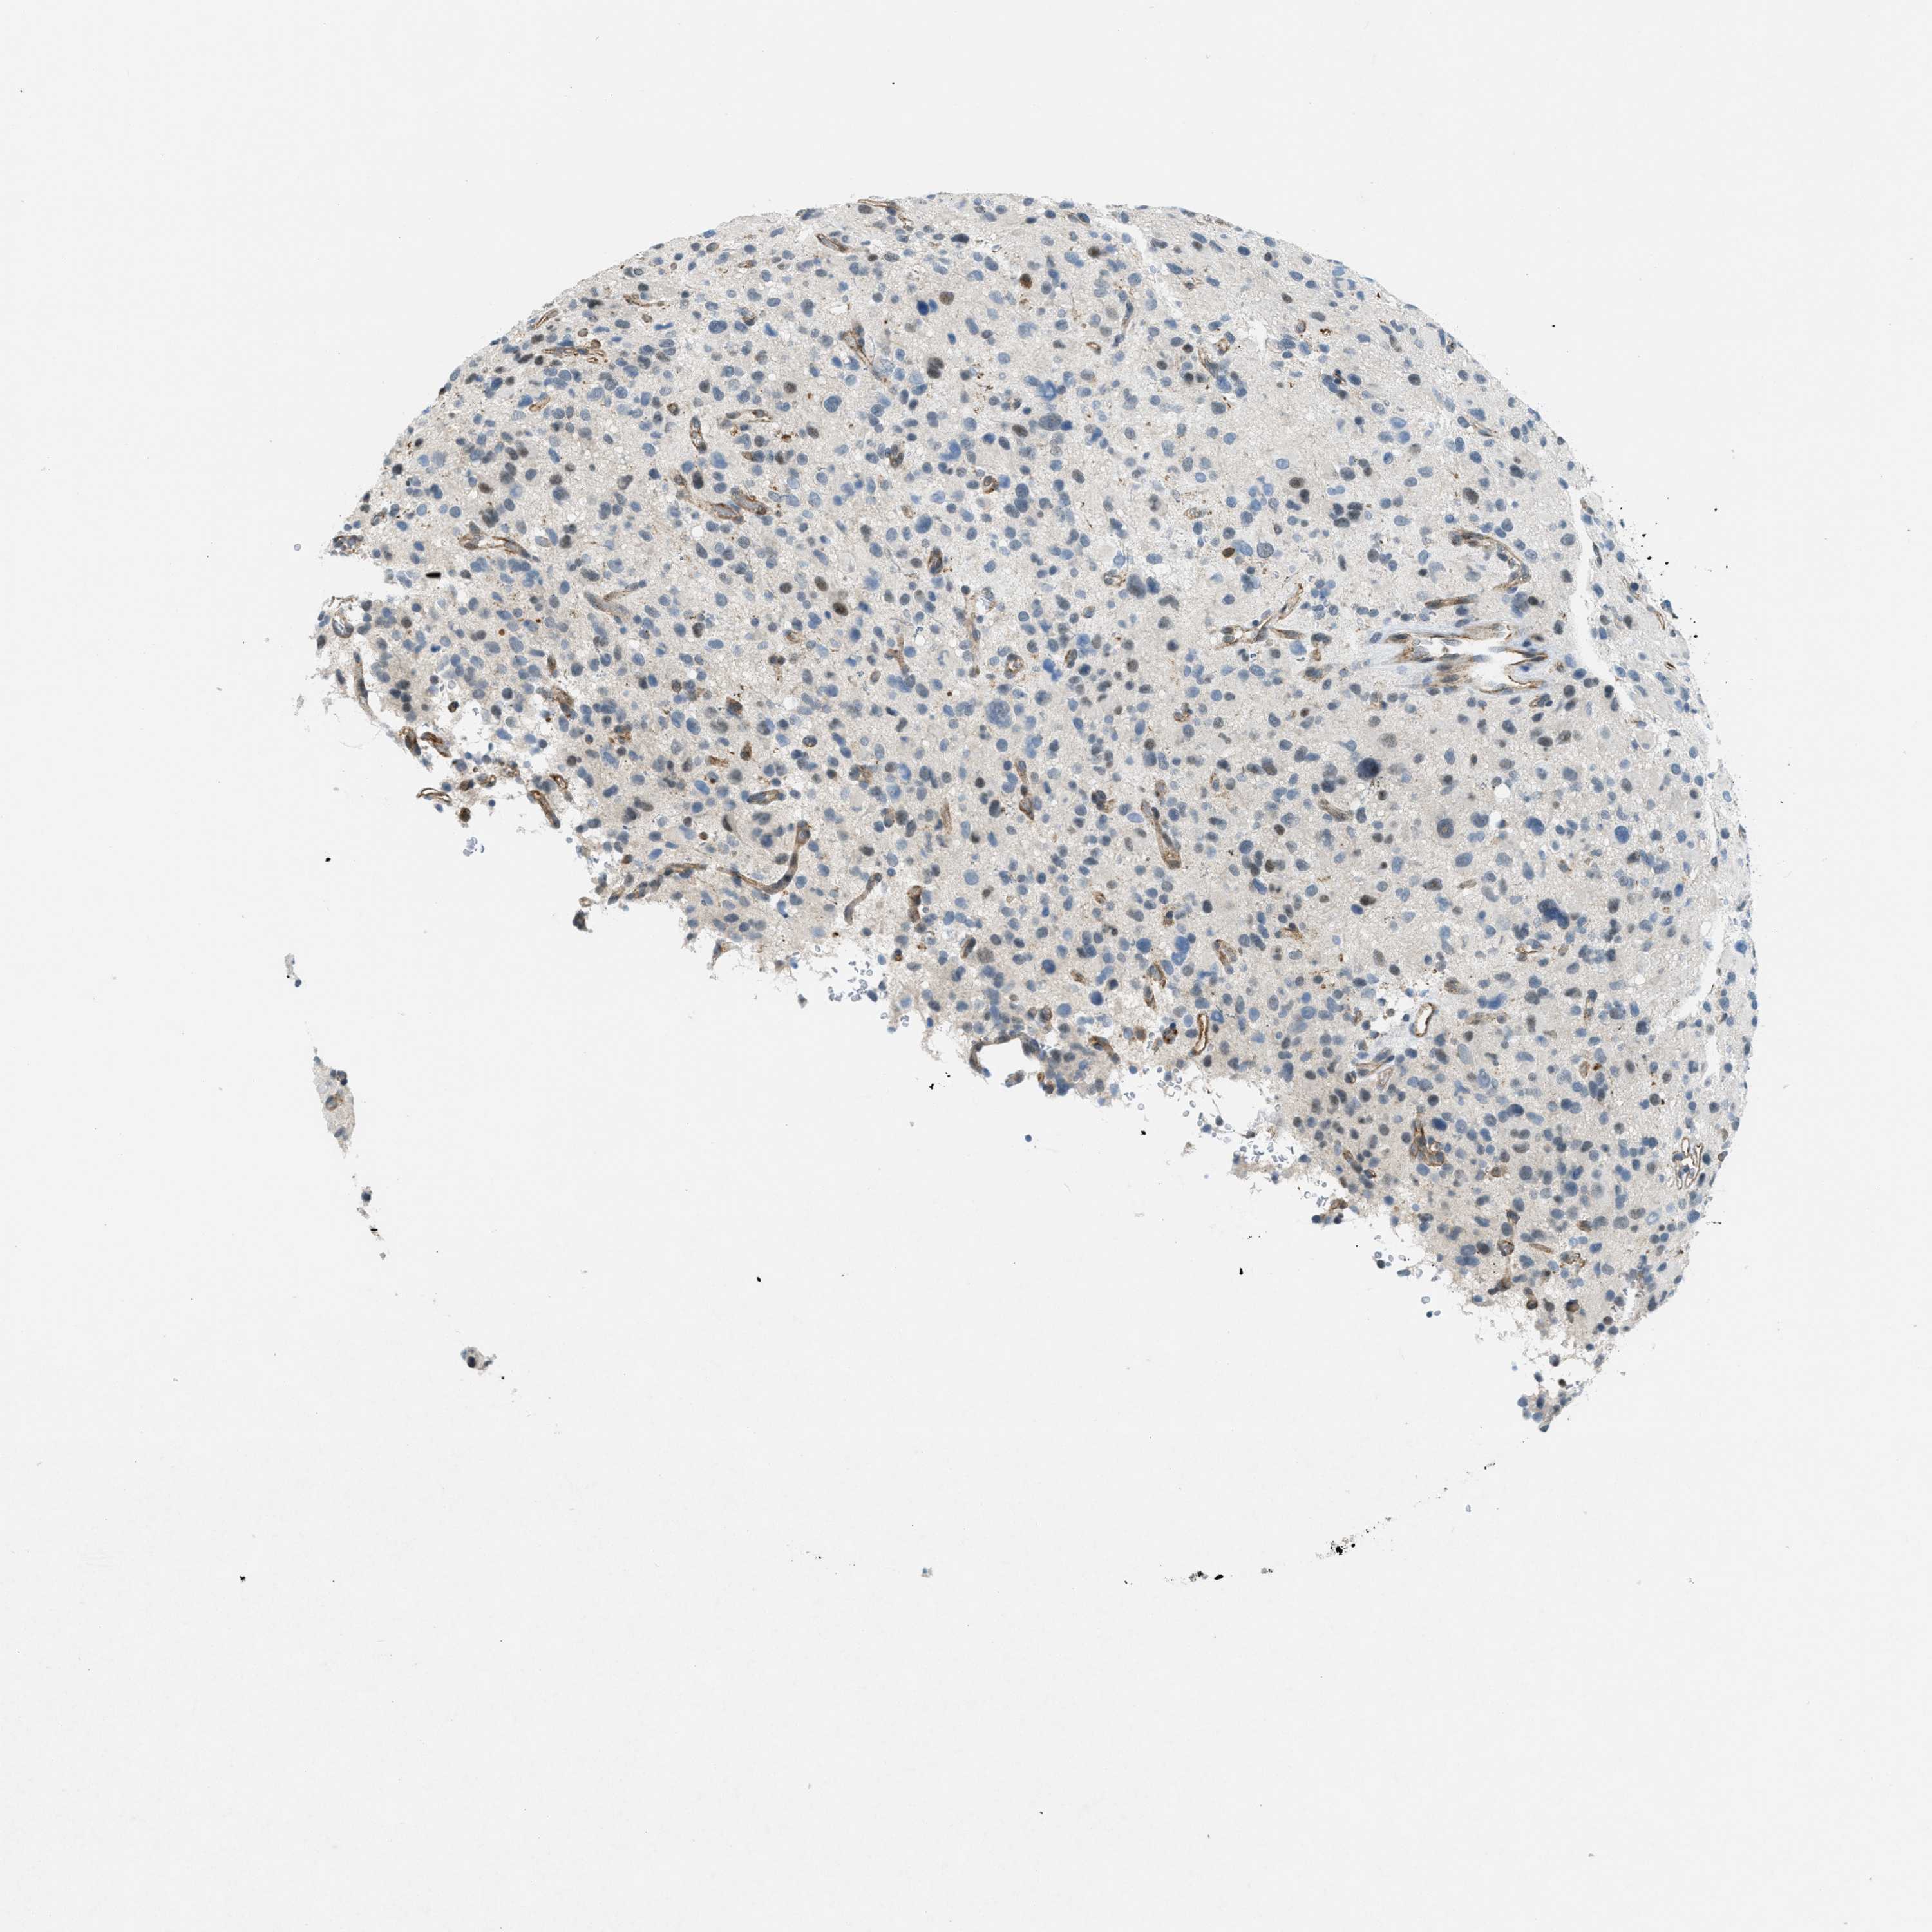

GLIOMA - Protein expressioni

A mouse-over function shows sample information and annotation data. Click on an image to view it in a full screen mode. Samples can be filtered based on level of antibody staining by selecting one or several of the following categories: high, medium, low and not detected. The assay and annotation is described here.

Note that samples used for immunohistochemistry by the Human Protein Atlas do not correspond to samples in the TCGA dataset.

Antibody stainingi

Antibody staining in the annotated cell types in the current human tissue is reported as not detected, low, medium, or high, based on conventional immunohistochemistry profiling in selected tissues. This score is based on the combination of the staining intensity and fraction of stained cells.

Each image is clickable and will lead to virtual microscopy that enables deeper exploration of all samples and also displays staining intensity scores, fraction scores and subcellular localization as well as patient and tissue information for each sample.

Antibody HPA023887

Antibody CAB005034

Antibody CAB018387

Staining

High

Medium

Low

Not detected

Intensity

Strong

Moderate

Weak

Negative

Quantity

>75%

75%-25%

<25%

None

Location

Nuclear

Cytoplasmic/membranous

Cytoplasmic/membranous,nuclear

Glioma, malignant, High grade

Glioma, malignant, Low grade

Glioma, malignant, NOS